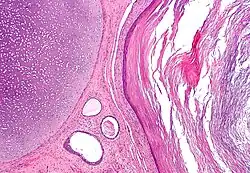

The endoderm is one of the germ layers formed during animal embryonic development. Cells migrating inward along the archenteron form the inner layer of the gastrula, which develops into the endoderm.

The endoderm consists at first of flattened cells, which subsequently become columnar. It forms the epithelial lining of the whole of the digestive tract except part of the mouth and pharynx and the terminal part of the rectum (which are lined by involutions of the ectoderm). It also forms the lining cells of all the glands which open into the digestive tract, including those of the liver and pancreas; the epithelium of the auditory tube and tympanic cavity; the trachea, bronchi, and alveoli of the lungs; the bladder and part of the urethra; and the follicle lining of the thyroid gland and thymus.

The mesoderm germ layer forms in the embryos of triploblastic animals. During gastrulation, some of the cells migrating inward contribute to the mesoderm, an additional layer between the endoderm and the ectoderm.[9] The formation of a mesoderm leads to the development of a coelom. Organs formed inside a coelom can freely move, grow, and develop independently of the body wall while fluid cushions protects them from shocks.[10]